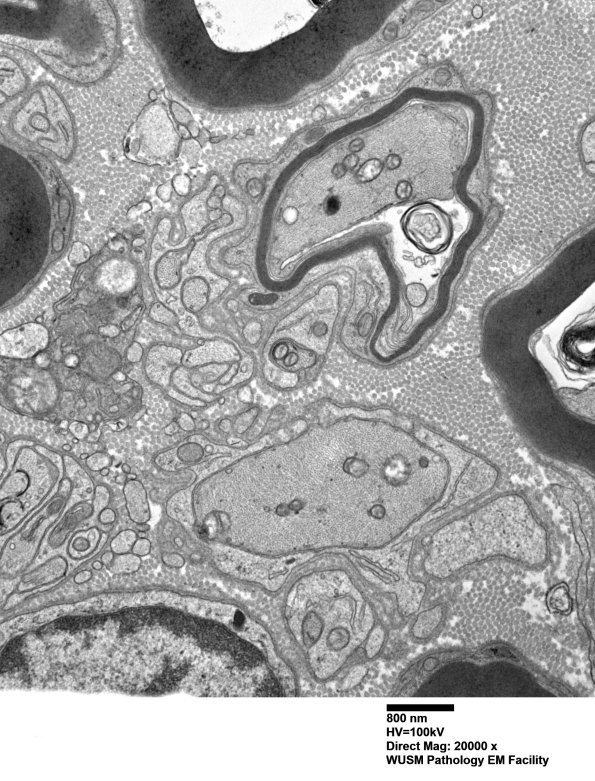

Washington University Experience | PERIPHERAL NEUROPATHY | 1 NORMAL NERVE ANATOMY | 6 Infant Peripheral Nerve | 2B12 W20-132 A (Case 2) tibial_018 - Copy

Pre-myelinated and thinly myelinated axons are numerous in this nerve which is developing rather than degenerating with very little debris. (electron micrograph)